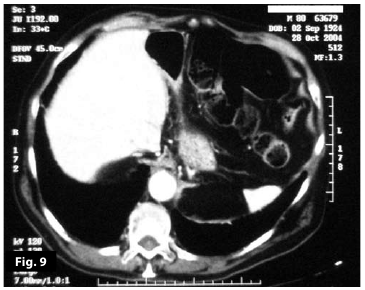

Figure9